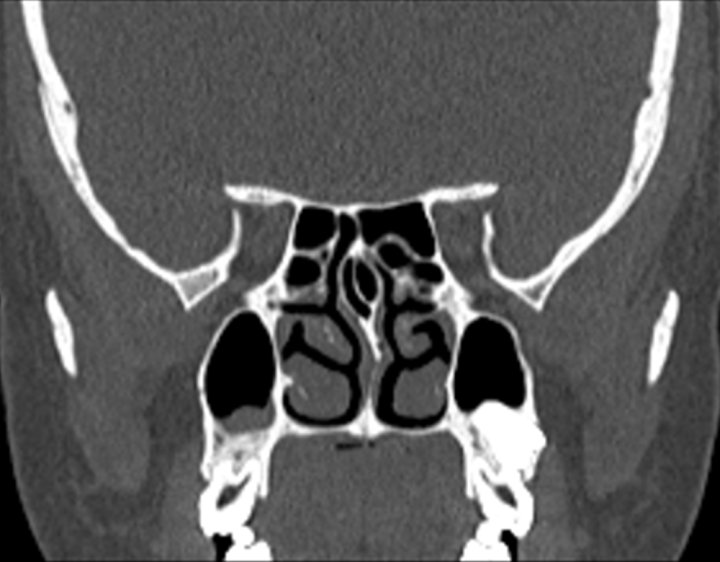

Click any image for labels.